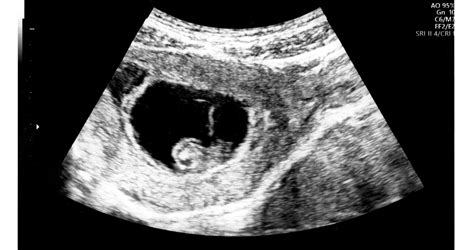

Mint már említettük, a tesztoszteron túltengés hátterében gyakran PCOS áll, ami a petefészkekben kialakult ciszták jelenlétére utal. Bár az esetek többségében a felnőtt nők kapcsán kerül szóba, ám gyerekeknél is előfordulhat, így tünetek fennállásakor náluk is érdemes erre gyanakodni. Ekkor a többek között a férfi hormonok túlsúlyba kerülése miatt nem megy végbe megfelelően a tüszőérés, így nem alakul ki domináns tüsző sem, ami megrepedhetne. Helyette apró, folyadékkal teli ciszták keletkeznek.

Egy páciens tapasztalata alapján: "Fél éve hagytam el a fogamzásgátlót és 3 hónapja volt egy nagyobb esztétikai műtétem. Tüneteim: hajhullás (szemöldököm is hullik), pattanások, pecsételő vérzés menzesz előtt. Vérvételem rendben, hormonális vérvétel rendben, pajzsmirigy rendben. Viszont nőgyógyászati ultrahangon "PCO szerű petefészekképek láthatóak". Csökkentett szénhidrát tartalmú diétát javasoltak. Tanácstalan vagyok mit kéne tennem."